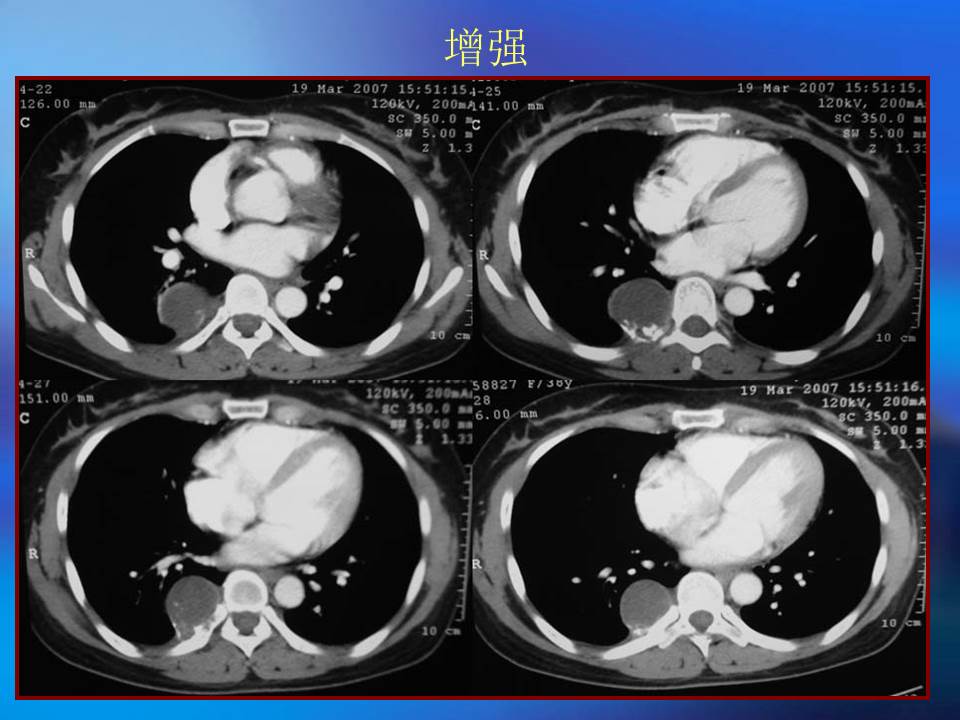

肺良性肿瘤